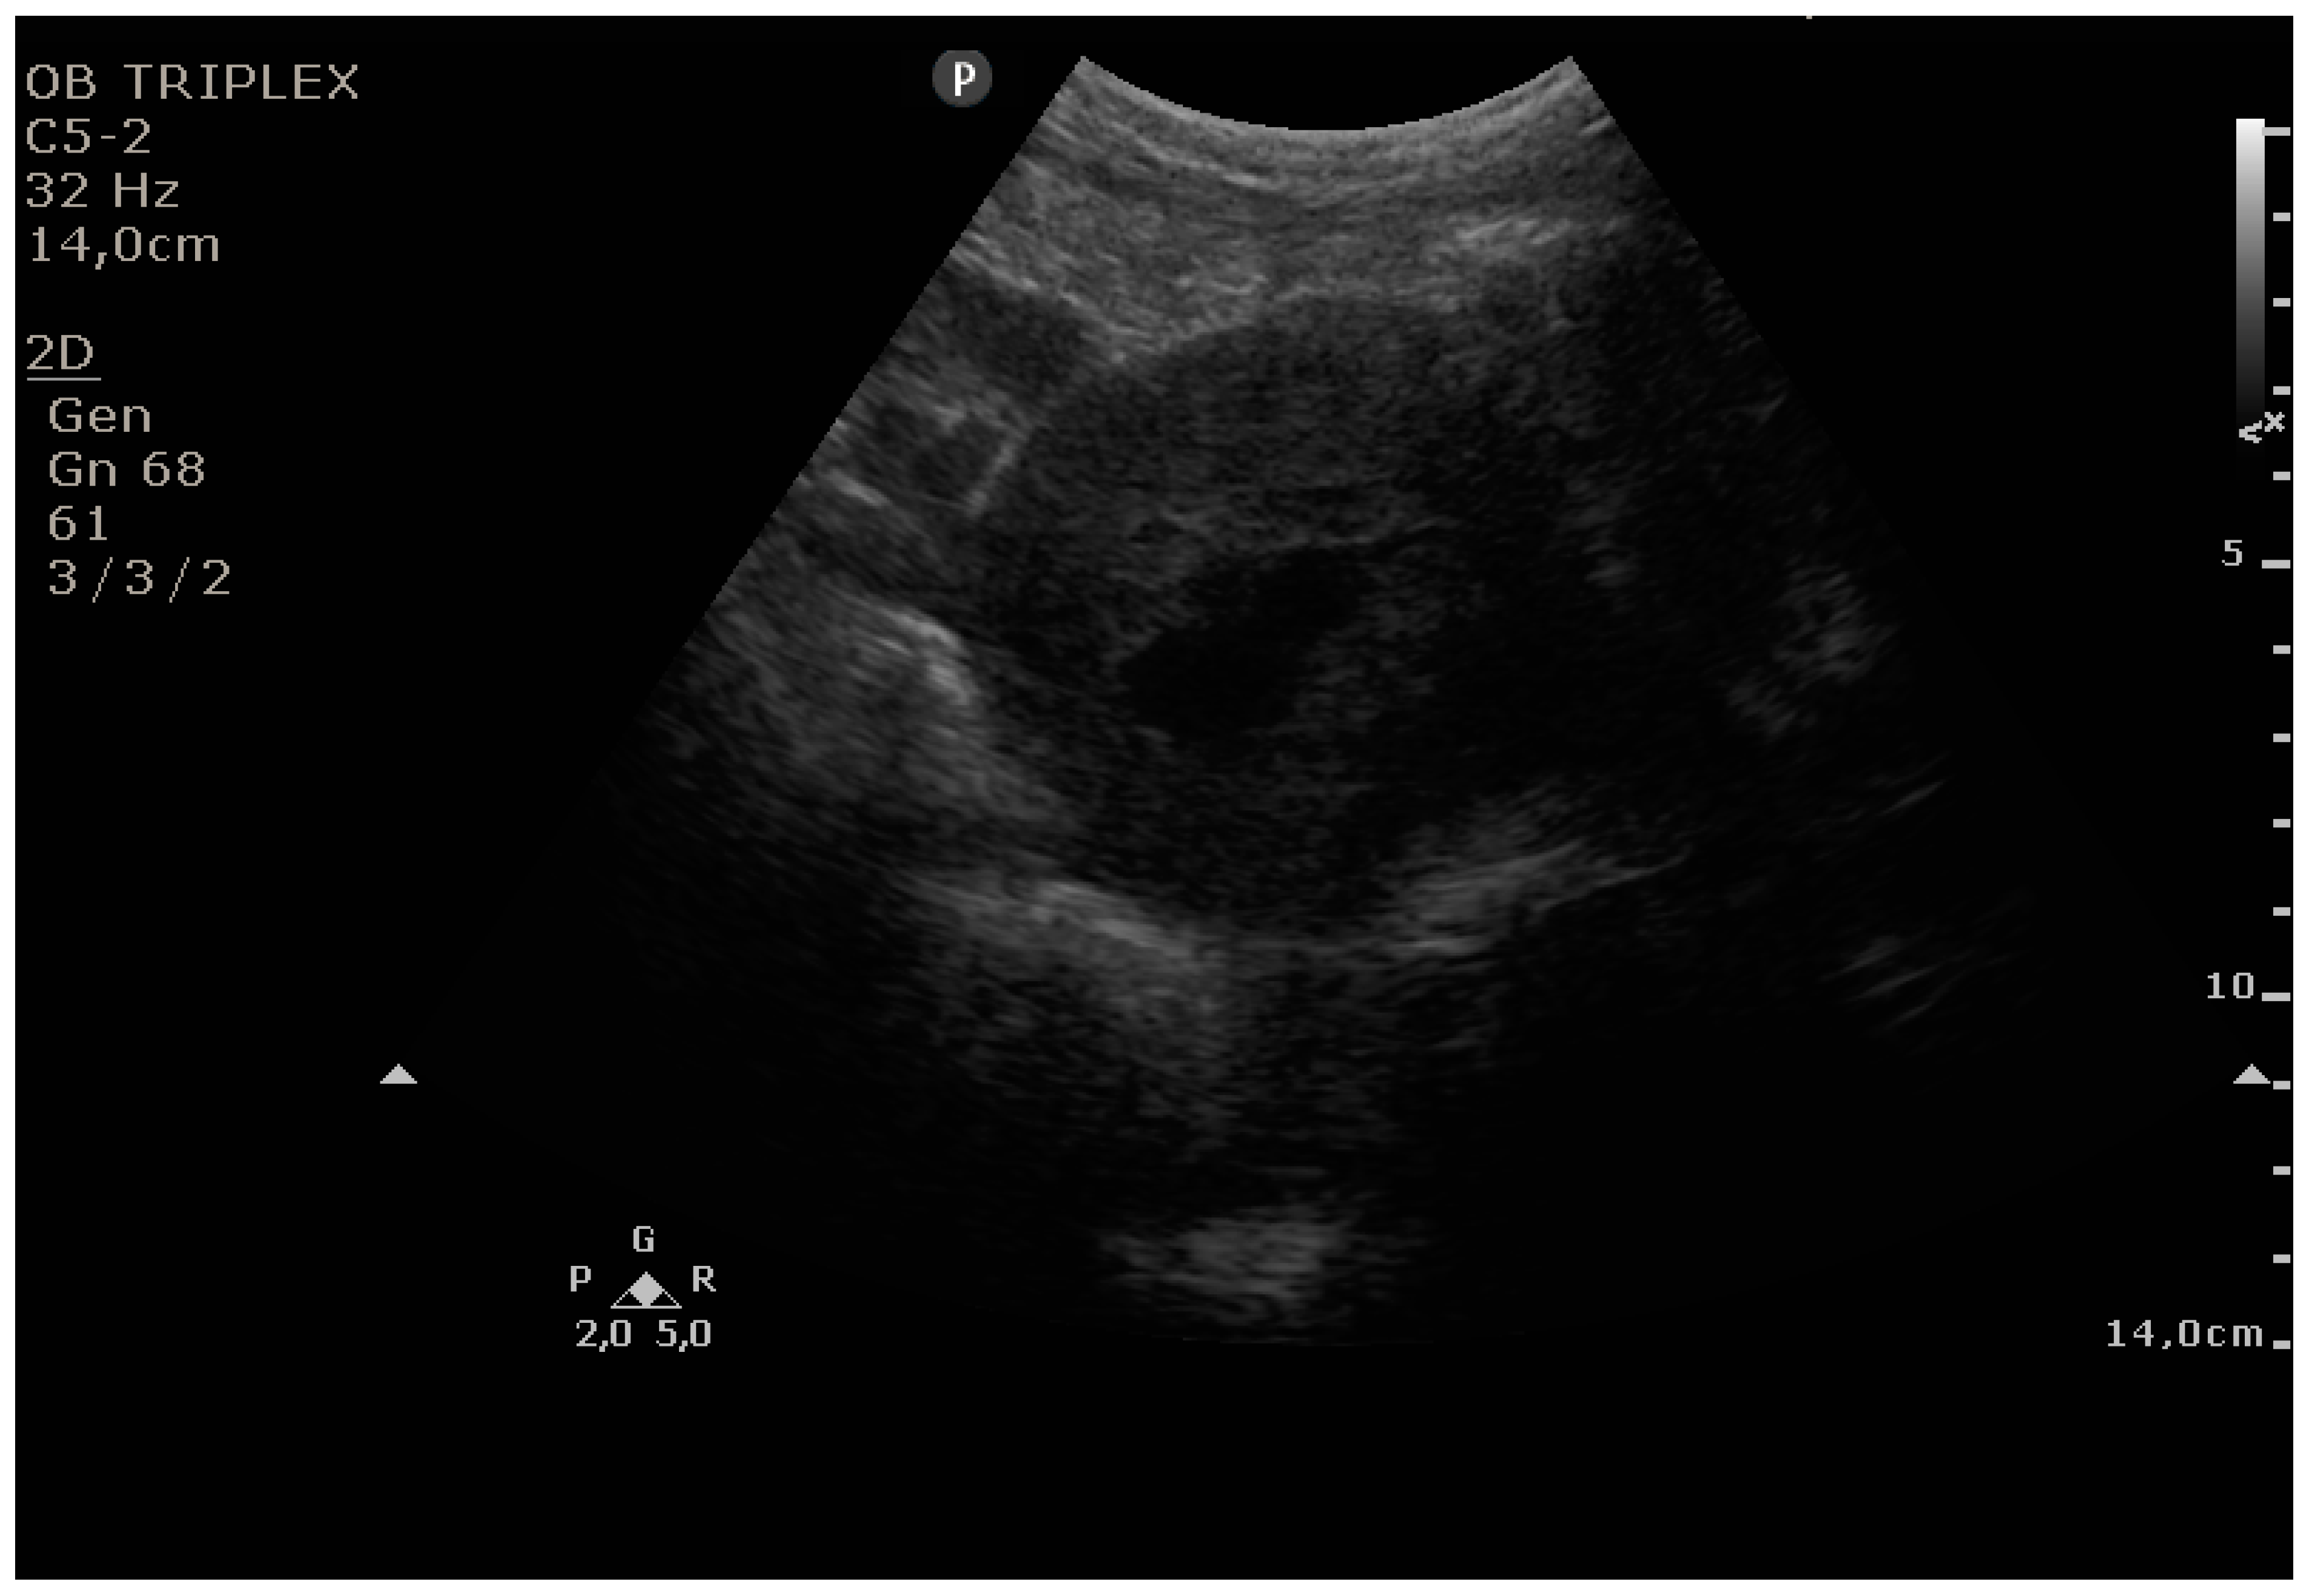

The PUUS method evaluates the proportion of the endometrial length occupied by blood or debris, as follows (Figure 1, Figure 2, Figure 3, Figure 4 and Figure 5):

Grade 3: less than three-quarters of the endometrial length occupied by blood or debris;

Figure 4. Grade 3: less than three-quarters of the endometrial length occupied by blood or debris.